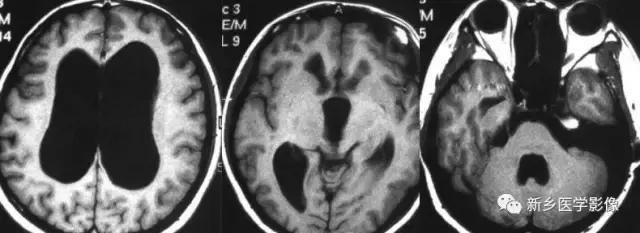

外伤后脑萎缩,感染后脑萎缩,脑梗死后脑萎缩CT可见扩大的脑室部分附近的脑实质呈片状低密度灶MR:T1WI呈低信号,T2WI呈高信号。同时脑沟及蛛网膜下腔增宽。

CT和MR均能够很好显示无脑回和巨脑回畸,表现为大脑半球表面几乎呈光滑状,仅可见少数宽阔、粗大、平坦的脑回,脑沟缺如.脑灰质增厚,脑白质变薄,灰白质分界面异常平滑,见不到白质向灰质内伸入的现象。常见透明中隔腔存在.侧脑室扩大,蛛网膜下腔增宽。